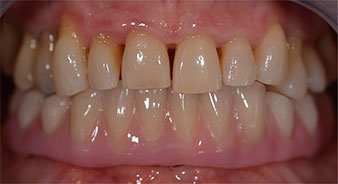

L'empreinte et l'enregistrement de l'occlusion ont ensuite été effectués afin que le prothésiste dentaire puisse commencer à réaliser la restauration provisoire. Celle-ci a été vissée le jour même (Fig. 17 et 18).

Après ostéointégration, l'empreinte finale des implants a été effectuée et la prothèse finale a été fabriquée en conséquence (Fig. 19 et 20). À cette étape, le praticien et le patient ont pu décider ensemble d'utiliser une facette dentaire en céramique ou en acrylique et une armature en zircone ou en métal. Dans ce cas, l'équipe du Dr Pascu a opté pour une facette dentaire en acrylique en raison du pronostic incertain de la denture maxillaire et du fait que la dent 24 est extrusée. Ce type de facette est plus facile à ajuster et peut donc être modifiée selon la nouvelle situation maxillaire.